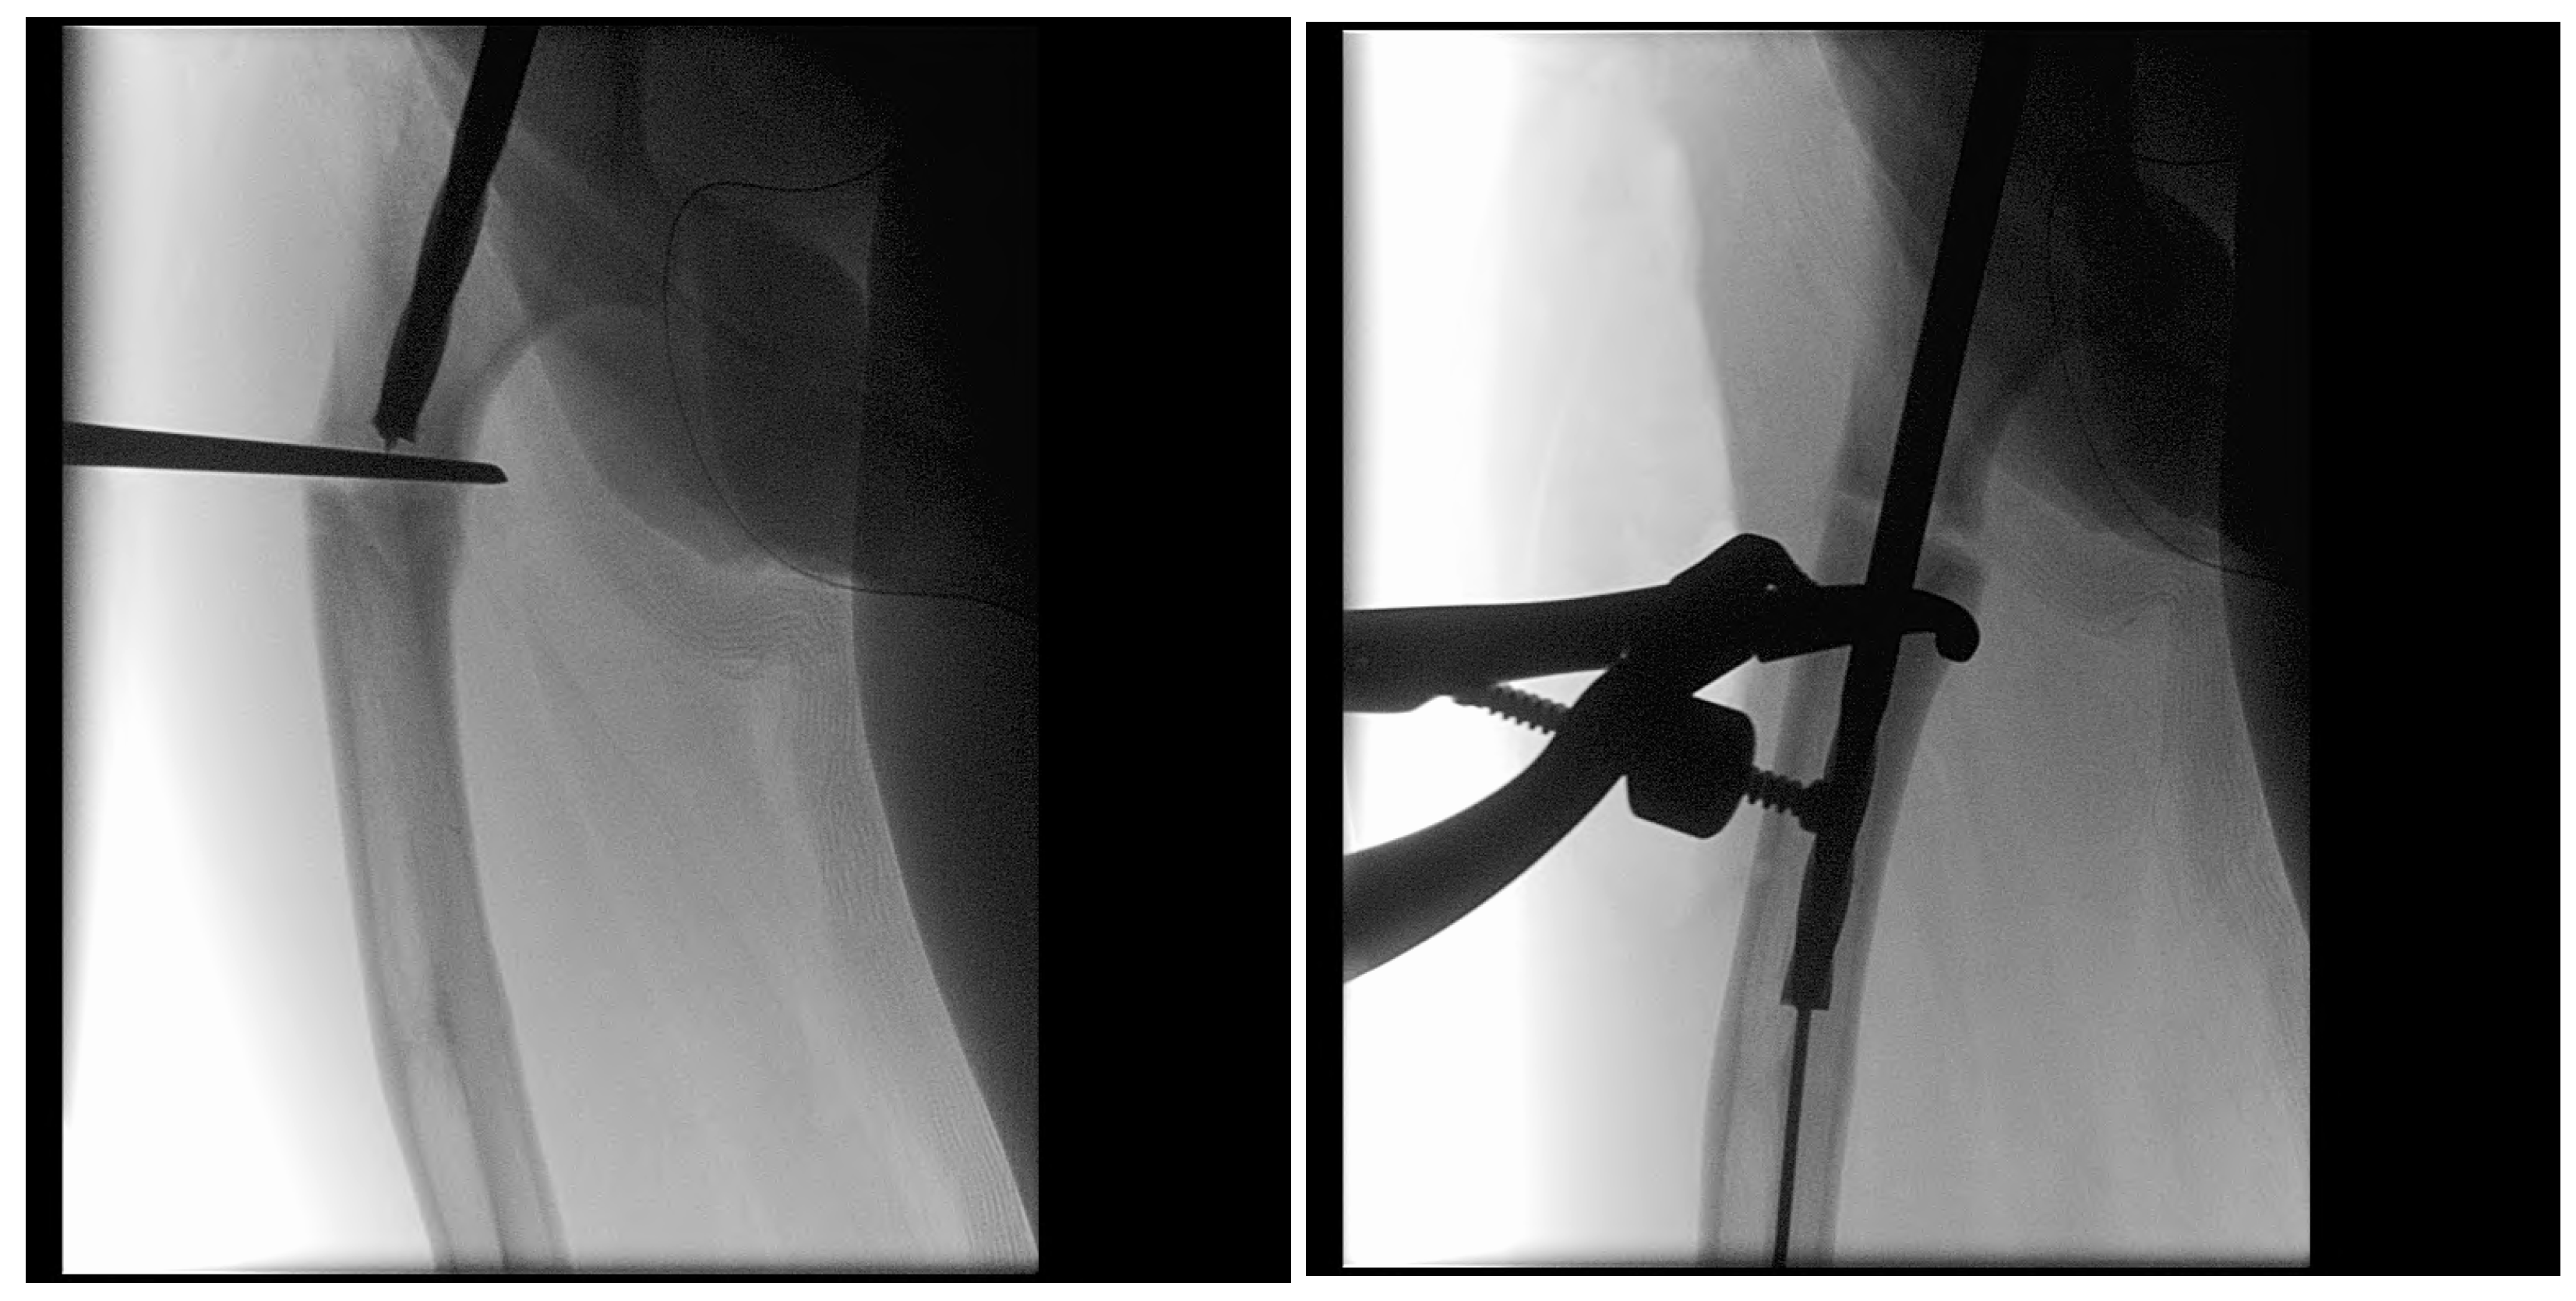

In the third case, a 16-year-old skeletally mature patient with OI was scheduled to undergo revision from FD rod to SLIM nail after presenting with pain due to stress fractures and wild deformity in his proximal right femur (Figure 11). The FD rod was removed, and then, using a piriformis entry point, access to the femur and proximal reaming was performed. There were two CORAs; the first CORA was identified in the subtrochanteric region, and a percutaneous osteotomy technique was performed to realign the bone, and then reaming was continued (Figure 12). The second CORA was identified, and another percutaneous osteotomy was performed, and the bone was cracked with a closed osteoclasis technique, and then reaming was continued in the distal segment (Figure 13). The SLIM nail was then inserted and had an excellent fit. The subtrochanteric region was under high stress, so a 2.7 Smith and Nephew EVOS plate to further stabilize the segment and control the rotation. Two screws were placed above and below (Figure 14). In this case, the indication for the use of the SLIM nail was the need to revise the existing telescoping FD rod in a skeletally mature patient to a solid nail. As the intramedullary canal was too small to accommodate a larger solid nail, a SLIM nail was used instead. The use of a plate as an adjunct to an intramedullary nail is also shown.

Intraoperative X-rays showing the first CORA and alignment with the continuation of the reaming.

Figure 13.

Intraoperative X-rays showing the second CORA and realignment with the continuation of the reaming.

Figure 14.

Post-operative X-ray showing SLIM nail and plate.